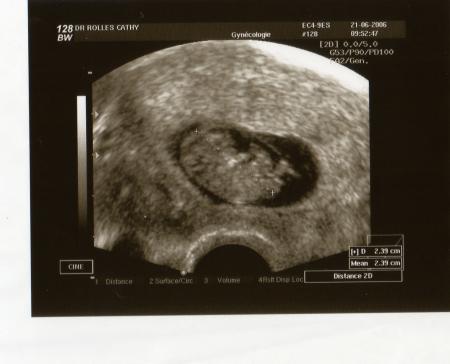

Voilà la 1ère écho à 7 semaines. Je suis prévu(e) pour le 2 février 2007.